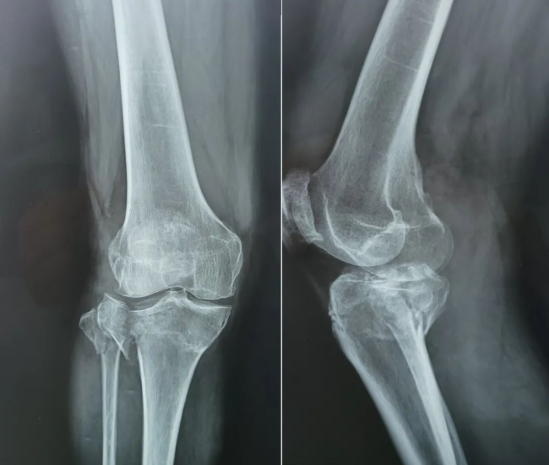

據(jù)了解,黃奶奶患有多年的骨性關(guān)節(jié)炎,疾病導(dǎo)致的疼痛程度不斷增加。平時(shí),行走緩慢、無(wú)法長(zhǎng)久站立、右側(cè)膝關(guān)節(jié)不能伸直等,已經(jīng)影響到正常的生活。

(骨性關(guān)節(jié)炎、粉碎性骨折)

近日,一次意外的跌倒導(dǎo)致黃奶奶右側(cè)膝關(guān)節(jié)粉碎性骨折,加上原本就患有的骨性關(guān)節(jié)炎,嚴(yán)重的傷情急需治療!

王教授說(shuō),“黃奶奶是脛骨平臺(tái)粉碎性骨折,骨折塌陷已經(jīng)傷到了關(guān)節(jié)平面。如果采用傳統(tǒng)手術(shù)方法,需要3塊鋼板進(jìn)行固定,不僅花費(fèi)多、恢復(fù)慢,康復(fù)后還會(huì)遺留疼痛、易發(fā)創(chuàng)傷性關(guān)節(jié)炎等問(wèn)題?!?/font>